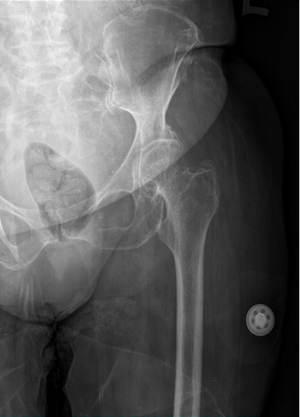

A 72-year-old female had a history of left hip trauma after tripping and falling at home. She was brought immediately to the emergency department and an anterior-posterior hip X-ray was done (Figure 1). As seen in the X-ray there was no sign of fracture but the clinical examination revealed pain at the left hip and limited mobility. Thus, considering the age of the patient, a pelvic CT scan was requested which also revealed no injury to the left hip (Figure 2). The patient was discharged and left home with anti-inflammatory and pain medication, being programmed to return after 7 days for a follow-up.

Figure 1: X-ray at the first presentation showing no fracture.